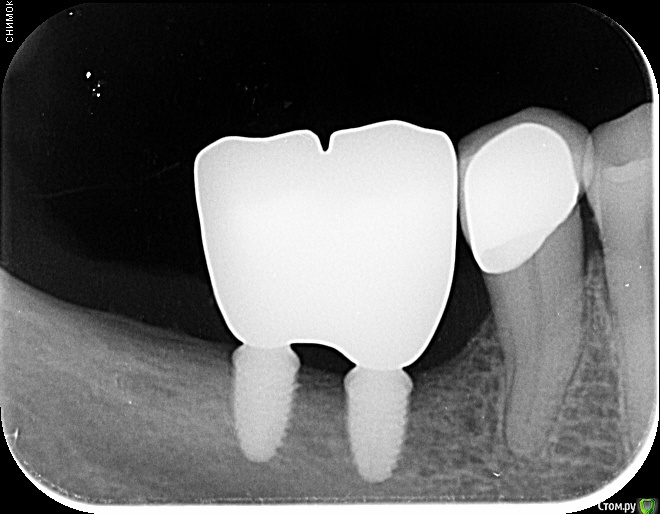

annda Опубликовано 3 августа, 2020 Поделиться Опубликовано 3 августа, 2020 (изменено) Стоял до этих имплантатов суперлайн коротыш 7мм,одиночка.Заколебались с раскруткой винта,ходила каждый месяц.Плюнула,решили выкрутить,переставить на эти.КТ после удаления. Изменено 3 августа, 2020 пользователем annda 1 Ссылка на комментарий

annda Опубликовано 4 августа, 2020 Поделиться Опубликовано 4 августа, 2020 Что-то с загрузкой пошло не так,извините.Контроль после постановки и контроль с абатментами(через 3 месяца) Ссылка на комментарий